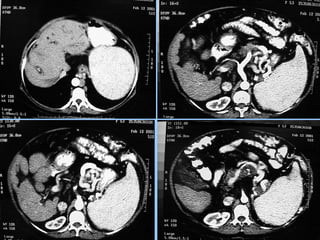

Abscessos Piogênicos

 S/C                 Fase portal

 Fase arterial         Fase portal

 Fase tardia

►s/c: Lesão grosseiramente arredondada, hipodensa

(0-45 HU), podendo conter septações e gás (sinal

específico, presente em menos de 20% dos casos).

Pode haver nível ar-fluido e fluido-debris.

►Realce anelar e/ou das        septações   após   a

administração do contraste.

►Pode haver derrame pleural e atelectasia de lobo

inferior direito.